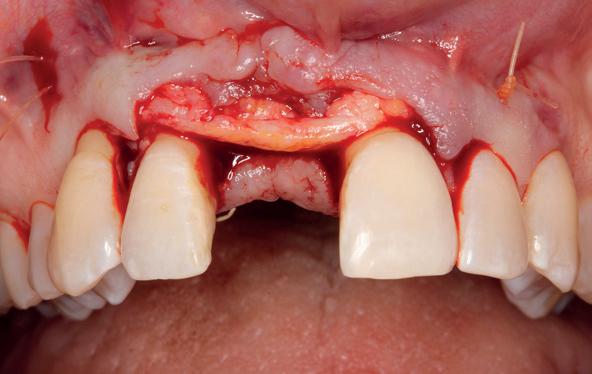

Implantologische behandelingen in het esthetische front vragen meer dan technische vaardigheid alleen. Ze vragen om overzicht, timing, vertrouwen en een team dat als vanzelf samenwerkt onder druk. Juist bij complexe casussen, waarin angst, infectie en hoge esthetische verwachtingen samenkomen, wordt zichtbaar hoe bepalend de rol van de tandartsassistent is.

Deze casus beschrijft een uitgebreide immediate implantaatbehandeling bij een patiënt die door meerdere collega’s werd geweigerd. Niet omdat de mogelijkheden ontbraken, maar omdat de complexiteit vroeg om een perfect afgestemde samenwerking. Het verhaal laat zien hoe de assistent in zo’n traject veel meer is dan een uitvoerende kracht of “mal”, maar een dynamische surgical guide die het proces mede stuurt, bewaakt en mogelijk maakt.De patiënt: wanneer alles samenkomt

Na het klinische onderzoek volgde het röntgenologisch traject. De CBCT liet precies zien wat we al vreesden: een front waarin het bot onregelmatig was, duidelijke radiolucenties rond de pijlers en een infectiegebied dat zich onder vrijwel de gehele brug had verspreid. Tegelijkertijd was er ook potentie. Net voldoende botstructuur om immediate implantaatplaatsing te overwegen, mits alles perfect gepland zou worden.